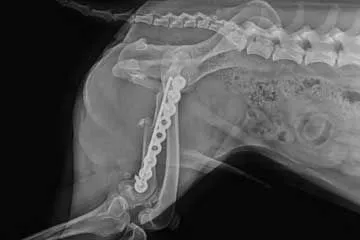

Kontrollröntgen nach erfolgreich verlaufener Operation.

Der „Fixateur” wurde von außen mit Drähten direkt an den Knochen angebracht.